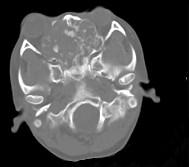

问题 男性,28岁,因鼻塞、头痛1年余,鼻窦CT扫描如图所示,请选择正确的描述与结论()

选项 A.双侧上颌窦、筛窦、鼻腔及蝶窦内见软组织肿块影 B.肿块内密度不均,有较多致密钙化影 C.窦壁及颅底骨质破坏 D.考虑鼻窦骨瘤 E.考虑为鼻窦软骨瘤

答案 ABCE